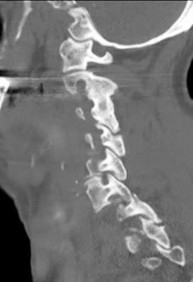

A 16-year-old male is brought to the clinic by his mother, who is concerned about his "round back." He complains of dull mid-back pain after standing for long periods. Standing lateral radiographs reveal a thoracic kyphosis of 65 degrees.

According to the Sorensen criteria, what specific radiographic finding is required to confirm the diagnosis of classic Scheuermann's disease?

A 16-year-old male presents with a stiff, painful thoracic hyperkyphosis that does not correct upon hyperextension. Standing lateral radiographs reveal anterior wedging of 4 consecutive thoracic vertebrae by 6 degrees each, along with irregular endplates and prominent Schmorl's nodes. Which condition is the most likely diagnosis?

A 15-year-old male presents with a progressive rounding of his back. Lateral radiographs are taken to evaluate for Scheuermann's kyphosis. According to the classic Sorensen criteria, which of the following radiographic findings confirms the diagnosis?

A 16-year-old male presents with cosmetic concerns regarding a "hunchback" posture. Radiographs reveal hyperkyphosis of the thoracic spine. To establish a formal radiographic diagnosis of Scheuermann's kyphosis (Sorensen criteria), what specific parameters must be met?